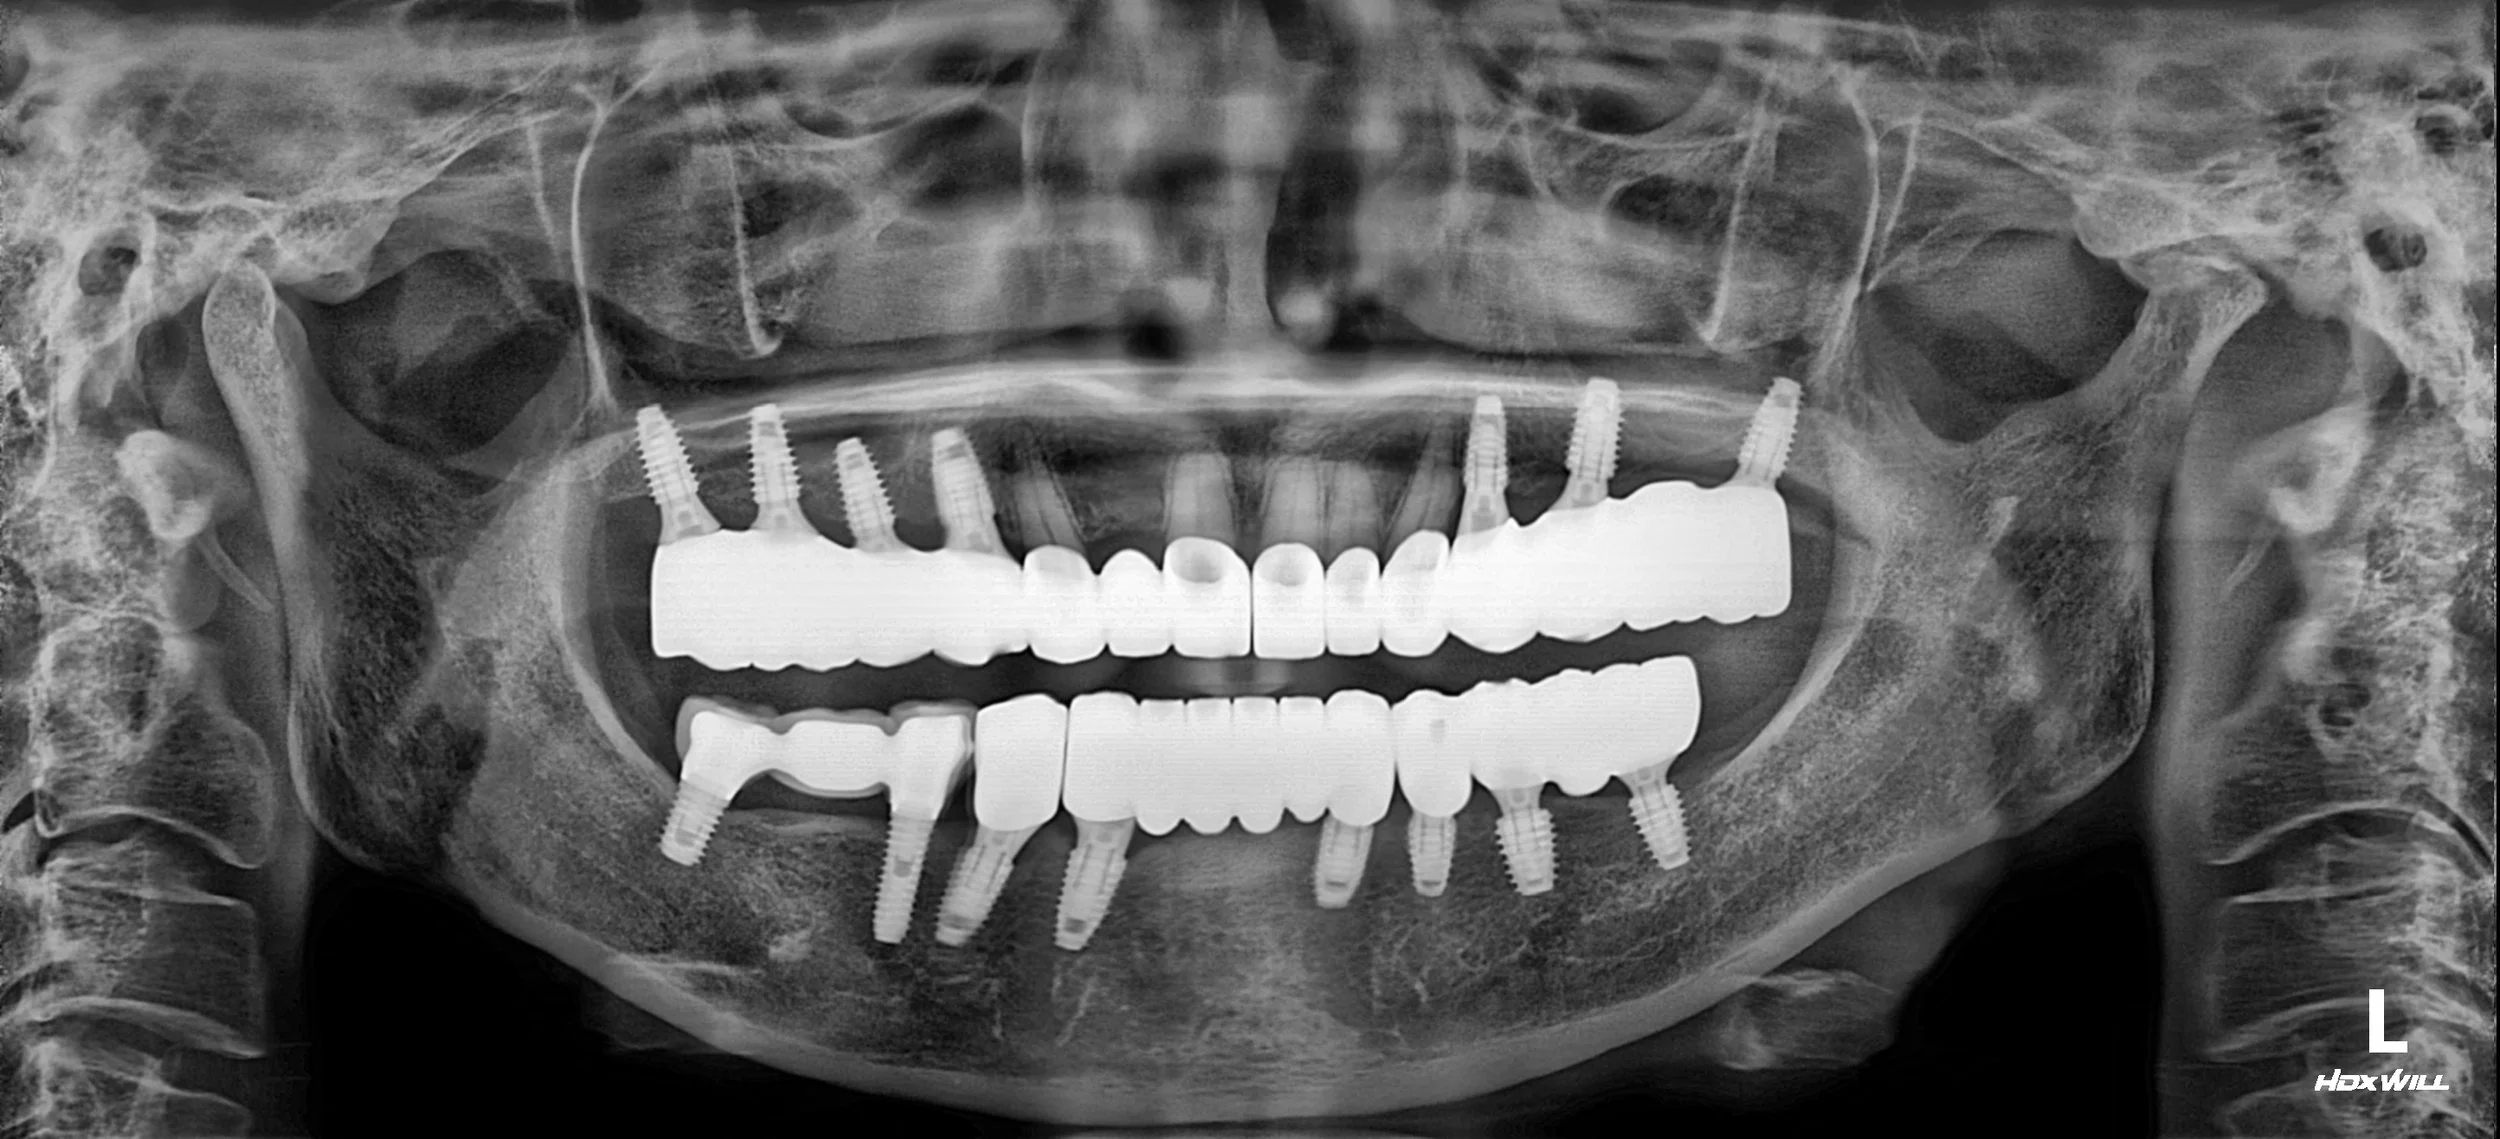

1. Surgical Foundation (Bilateral Sinus Lifts): Due to the lack of bone height in the upper posterior segments, extensive sinus bone grafting was performed on both sides. This provided the necessary foundation for the subsequent implant surgery.

2. Implant-Driven Reconstruction: Dental implants were strategically placed across both arches to replace failing teeth and existing problematic implants. These served as the new "occlusal stops" for the reconstruction.

3. VDO Management & Adaptation: The patient's vertical dimension was systematically raised using long-term provisional restorations. This phase allowed for the stabilization of the TMJ and neuromuscular system, ensuring the new bite height was both comfortable and reproducible.

4. Final Definitive Delivery: Once functional stability and gingival health were verified, the final high-precision zirconia bridges and crowns were delivered. The result is a healthy, maintainable oral environment with a balanced occlusion and a naturally rejuvenated aesthetic profile.